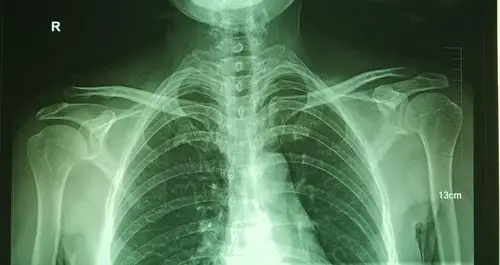

肩锁关节脱位Ⅲ型,喙锁韧带重建手术 - 好大夫在线